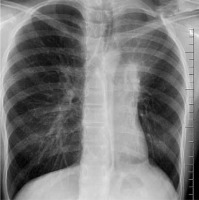

Herein we present a case of a 13-year-old girl who was admitted to the Department of Paediatric Surgery, Traumatology, and Urology in Poznan. She reported chest discomfort, difficulty breathing, and a cough. A month prior to admission she had suffered from a respiratory tract infection. She was delivered at term as a firstborn child with an Apgar score of 10 and a normal birthweight of 3360 g. At the age of three years, she was diagnosed with erythrocyturia. Clinical examination on admission revealed pallor, left side rib prominence, and diminished vesicular breath sounds on the left (from base to shoulder blade angle). X-ray showed atelectasis of a large part of the superior left lobe and obstruction of the bronchus leading to the third segment of the left lung (Fig. 1).

Fig. 1

X-ray showed atelectasis of almost the whole left lung superior lobe and obstruction of the bronchus leading to the third segment of the left lung